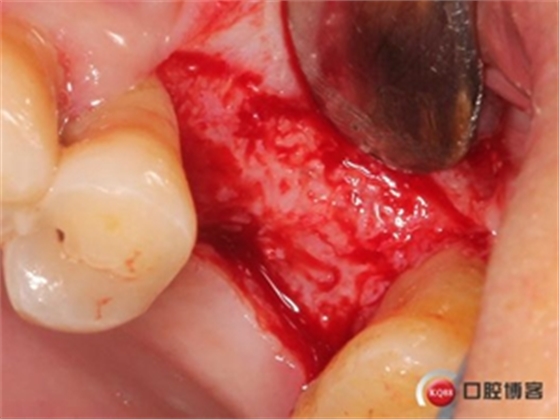

使用水壓系統(tǒng),將1ml左右生理鹽水緩慢注入開孔內(nèi)。

1ml水量便可將頰側(cè)上頜竇膜在還沒有開窗剝離之前就已經(jīng)與上頜竇頰側(cè)骨壁剝離開來,所以此時再在開孔處開窗將不用再擔(dān)心會傷及上頜竇膜。用環(huán)切開窗鉆,將種植機調(diào)成反轉(zhuǎn)模式、轉(zhuǎn)速調(diào)至200-500轉(zhuǎn)之間。

無需全部磨穿,剩余一些骨量既可以。

將骨片撬開并取下。

還沒有進行竇膜剝離,頰側(cè)上頜竇膜已經(jīng)和骨壁有效分離。

擴大窗口,進一步剝離竇膜。

植入骨粉。